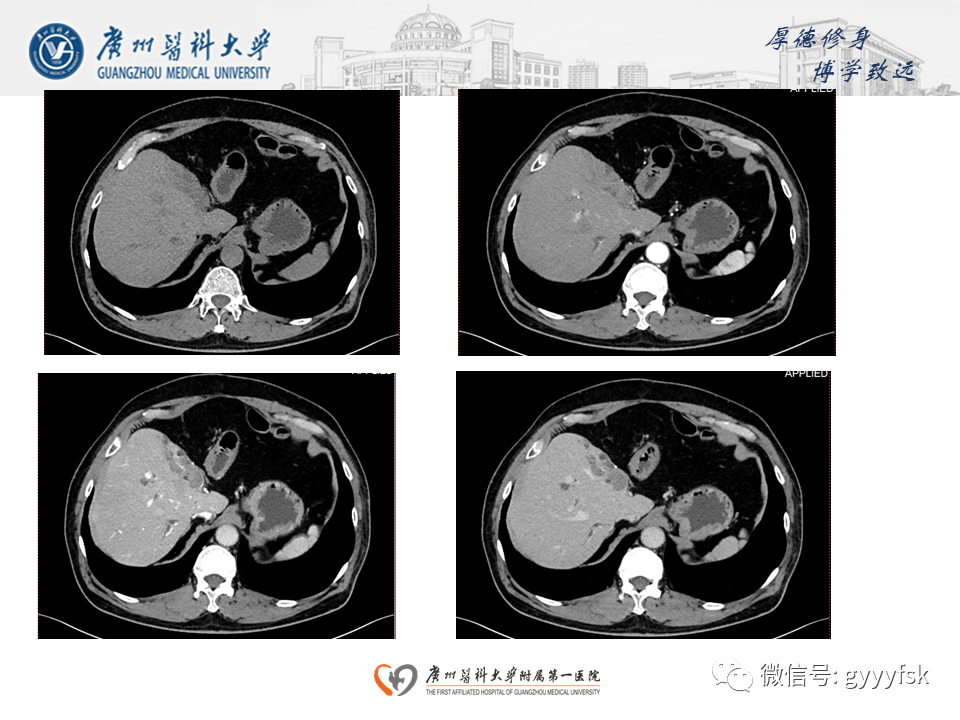

胆管导管内乳头状肿瘤(IPNB)